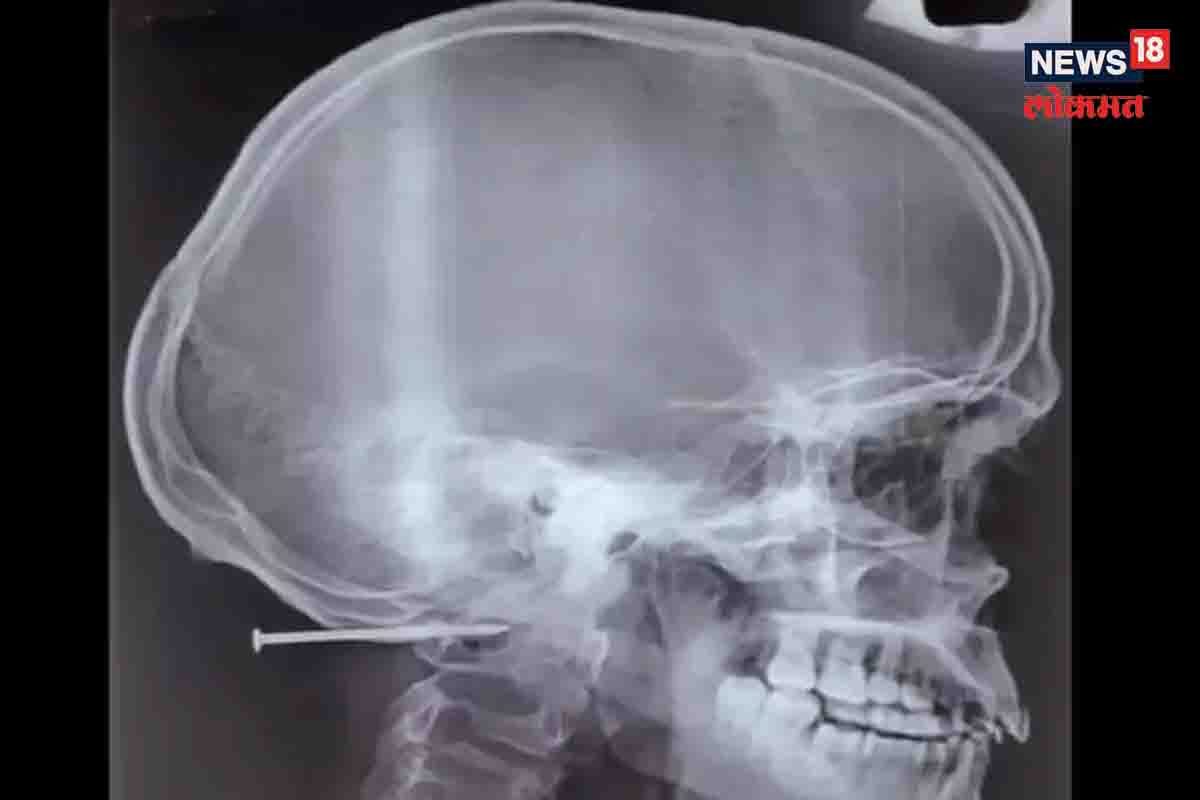

चेन्नई, 15 जून : वैद्यकीय क्षेत्रातल्या अचंबित करणाऱ्या घटनांविषयी आपण बरेचदा ऐकतो. एखाद्या भीषण अपघातात किंवा घटनेतून एखादी व्यक्ती वैद्यकीय उपचारांमुळे आणि डॉक्टरांच्या प्रयत्नांमुळे मृत्यूच्या दाढेतून परतल्याचे आपण पाहतो. उत्तर प्रदेशातल्या एका कामागाराची कहाणी अशीच काहीशी आहे. प्रगत वैद्यकीय उपचार आणि डॉक्टरांच्या प्रयत्नांमुळे ही व्यक्ती अक्षरशः मृत्यूच्या दाढेतून परतली आहे. काम करताना एका सहकाऱ्याच्या हातून नेल गन लागल्याने या व्यक्तीच्या डोक्याच्या मागच्या बाजूला दोन इंचाचा खिळा घुसला होता. पण अवघड शस्त्रक्रियेनंतर ही व्यक्ती आता पूर्ण बरी झाली आहे. ही घटना नेमकी कशी घडली,ते सविस्तर जाणून घेऊया.`टाइम्स ऑफ इंडिया`ने या विषयीची माहिती दिली आहे. एका खासगी रुग्णालयातील डॉक्टरांनी एका व्यक्तीला सहा तासांच्या अवघड शस्त्रक्रियेनंतर जीवदान दिलं. एका कामागाराच्या डोक्यातला दोन इंची खिळा बाहेर काढण्यात डॉक्टरांना यश आलं. चार जुलैला कारखान्यातल्या एका सहकाऱ्याकडून नेल गन चुकून मागे लागली. तेव्हा त्या गन मधला खिळा या व्यक्तीच्या डोक्याच्या बाजूला घुसला. डॉक्टरांनी खिळा काढण्यासाठी या व्यक्तीच्या डोक्याला छिद्र पाडलं. या अवघड शस्त्रक्रियेनंतर सहा जुलै रोजी या व्यक्तीला रुग्णालयातून डिस्चार्ज देण्यात आला. उत्तर प्रदेशातल्या मछली गावातील 23 वर्षांच्या ब्रह्मासोबत ही घटना घडली. या अपघातातून तो आश्चर्यकारकरित्या बचावला. शस्त्रक्रिया झाल्यावर दोन दिवसांनी ब्रह्मा चालू लागला. तो चालत रुग्णालयाच्या कॉन्फरन्स रुममध्ये आला. या वेळी माध्यमांच्या कॅमेऱ्यांनी त्याच्या चेहऱ्यावरचं हास्य टिपलं.``डॉक्टरांनी आता टाके काढले आहेत,``असे ब्रह्माने पत्रकार परिषदेत बोलताना सांगितलं.``मी खाऊ शकतो,चालू शकतो तसंच सहजपणे बोलूही शकतो. मला आता खूप चांगलं वाटत आहे. मी आता पुन्हा कामावर जाण्यासाठी उत्सुक आहे,``असं ब्रह्माने सांगितलं. ``शस्त्रक्रिया झाल्यावर ब्रह्मा शुद्धीवर आला. तो सावध होता. तसंच त्याला हातापायाची हालचाल करण्यास कोणतीही अडचण येत नव्हती. त्याला दुसऱ्याच दिवशी रुग्णालयातून डिस्चार्ज देण्यात आला. आता तो पूर्वीप्रमाणे त्याचं काम करू शकतो,``असे डॉक्टरांनी घोषित केल्याची माहिती रेला रुग्णालयाचे सीईओ डॉ. इलनकुमारन कालियामूर्ती यांनी दिली. वाचा - पीसीओएसच्या समस्येमुळे गरोदर राहण्यात अडचणी येतात? जाणून घ्या तज्ज्ञ काय सांगतात 4 जुलै रोजी हा अपघात घडला. नवलूर येथील कारखान्याच्या पॅकेजिंग युनिटमध्ये ब्रह्मा फरशी साफ करत होता. त्यावेळी त्याचे सहकारी नेल गनने लाकडी खोकी सील करत होते. त्यावेळी ब्रह्माने त्याच्या डोक्याच्या मागच्या बाजूला अचानक तीव्र वेदना झाल्याची तक्रार केली. त्याला तीव्र रक्तस्त्राव होत होता. फ्लोअरवरील कर्मचाऱ्यांनी त्याला शांत केले. या वेळी त्यांना एक खिळा दिसला. या खिळ्याचा आकार पेन्सिल सेल एवढा होता. हा खिळा ब्रह्माचं डोकं आणि मान यांमधल्या भागात घुसला होता. खिळा सहकाऱ्याच्या नेल गनमधला असल्याचं लक्षात आलं. ``त्यानंतर ब्रह्माला रेला रुग्णालयाच्या आपत्कालीन विभागात दाखल करण्यात आले. त्यावेळी तो शुद्धीवर आणि सावध होता. त्याच्या हातापायात अशक्तपणा जाणवत नव्हता. त्याचे ब्लडप्रेशर आणि पल्स रेट नॉर्मल होता. ही गोष्ट आणि त्याचं कमी वय हा आमच्यासाठी मोठा फायदेशीर घटक ठरला,``असं रुग्णालयाचे कन्सल्टंट न्यूरोसर्जन डॉ. एम. अन्बुसेल्वम यांनी सांगितलं. ``परंतु, हा खिळा ब्रह्माच्या कवटी आणि मणक्याच्या क्रॅनीओव्हर्टिब्रल जंक्शन कॉम्प्लेक्स ट्रान्सिशनल झोनमध्ये त्वचेच्या किमान अर्धा इंच आत होता. या ठिकाणी विविध घटकांचे जटिल संतुलन असते. हा खिळा डाव्या बाजूच्या व्हर्टिब्रल आर्टरी जवळ होता. यामुळे तिथे इजा झाल्यास बोलण्यात समस्या,पॅरालिसिस किंवा प्रसंगी मृत्यूही होऊ शकला असता,``असे डॉ. अन्बुसेल्वम म्हणाले. ``सीटी स्कॅनमध्ये हा खिळा साधा किंवा लहान नसल्याचे दिसून आले. लाकडात हातोड्याने ठोकल्यानंतर हा खिळा सहजपणे काढता येऊ नये किंवा त्याला कुठलीही बाधा होऊ नये अशा दृष्टिने खिळ्याच्या खालचा भाग डिझाईन केलेला होताखिळ्याचा खालचा भाग आटे नसल्याने गुळगुळीत होता व त्याला काही अटॅचमेंटही होती,``असं डॉक्टर अन्बुसेल्वम यांनी सांगितलं. त्यामुळे ब्रह्मावर तातडीने शस्त्रक्रिया करण्याचा निर्णय घेण्यात आला.``रुग्णाचे चेहरा बेडवर टेकवून हा खिळा हळूवारपणे काढता यावा यासाठी डॉक्टरांनी डायमंड बर्र नावाच्या विशेष न्यूरोसर्जरी उपकरणाचा वापर केला. या उपकरणामुळे सावकाशपणे खिळ्याच्या बाजूला ड्रिलिंग करणं शक्य झालं. खिळ्याचा खालचा गुळगुळीत भाग उघडा पडल्यावर ड्रिलिंग करून हा खिळा हळूवारपणे काढण्यात आला आणि सहा तासांच्या शस्त्रक्रियेनंतर रुग्णाचे प्राण वाचले,``असे डॉक्टरांनी सांगितले.